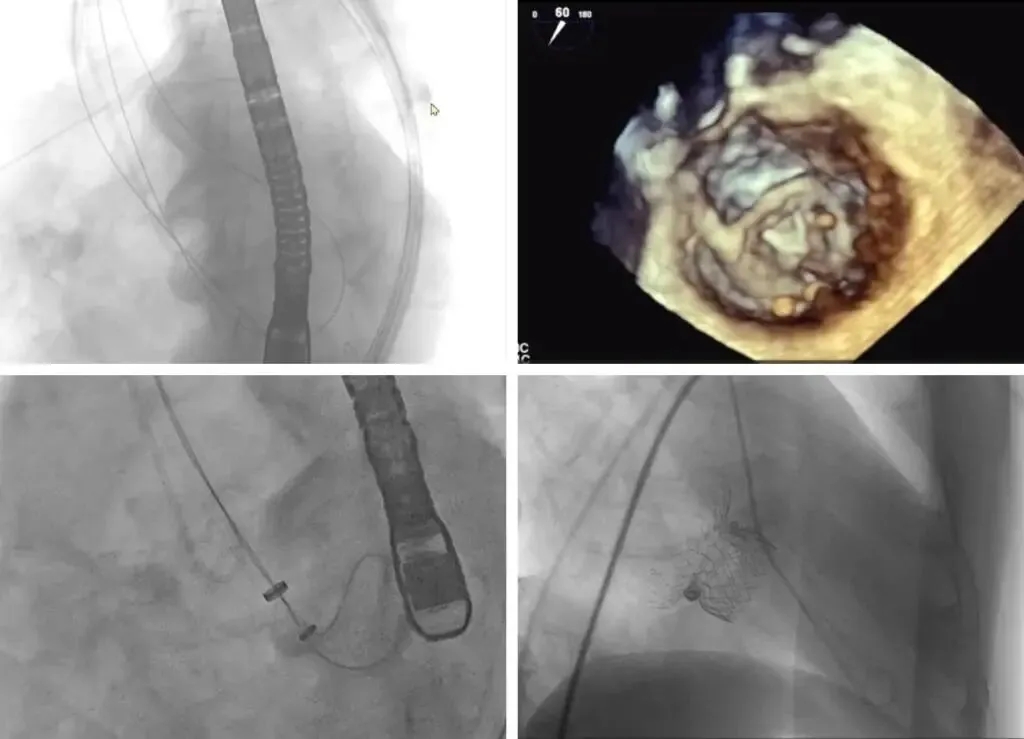

注意Trap识别与绕环位置确认;因左心房明显增大,避免房间隔穿刺位置过高。此例已经充分GDMT治疗,具备二尖瓣手术干预指征,决定使用HighLife系统行经股静脉房间隔二尖瓣置换术。此次手术主要包含三大步骤,逆行主动脉路径,利用导丝围绕原生二尖瓣成环;沿导丝轨道完成固定环植入;经房间隔路径植入人工瓣膜。

术中,经左股动脉入路,在术前规划的DSA投射体位和超声引导配合下确认绕环导管初始深度,前进导丝绕过外交界-P3-P2-P1-内交界后,随血流跨主瓣返回升主动脉,在升主动脉使用snare抓捕。为了更充分地验证导丝成环轨道,术者在DSA与超声影像的共同指引下,清晰地观察到导丝均匀地向二尖瓣环与中心收紧。整个过程快速且一气呵成,术者顺利避开预估的所有Trap,为后续固定环的植入建立了确切的轨道。轨道建立后,固定环输送器沿着成环导丝经主动脉瓣推送至左心室,将固定环从输送器中推出,收紧导丝两端并完成固定环扣合。最后,在建立房间隔入路后,经右股静脉送入 HighLife瓣膜,在DSA的指引下先缓慢释放人工瓣膜心室端,后回拉输送器将瓣膜心室端与固定环贴紧二尖瓣环,并快速释放瓣膜心房端。在固定环的辅助下,人工瓣膜于二尖瓣瓣环平面完成自同轴展开释放,最后逐步撤出输送器。即刻超声评估提示二尖瓣反流完全消失,无瓣周漏,无左室流出道梗阻,人工瓣膜植入位置理想,形态良好。手术顺利结束。